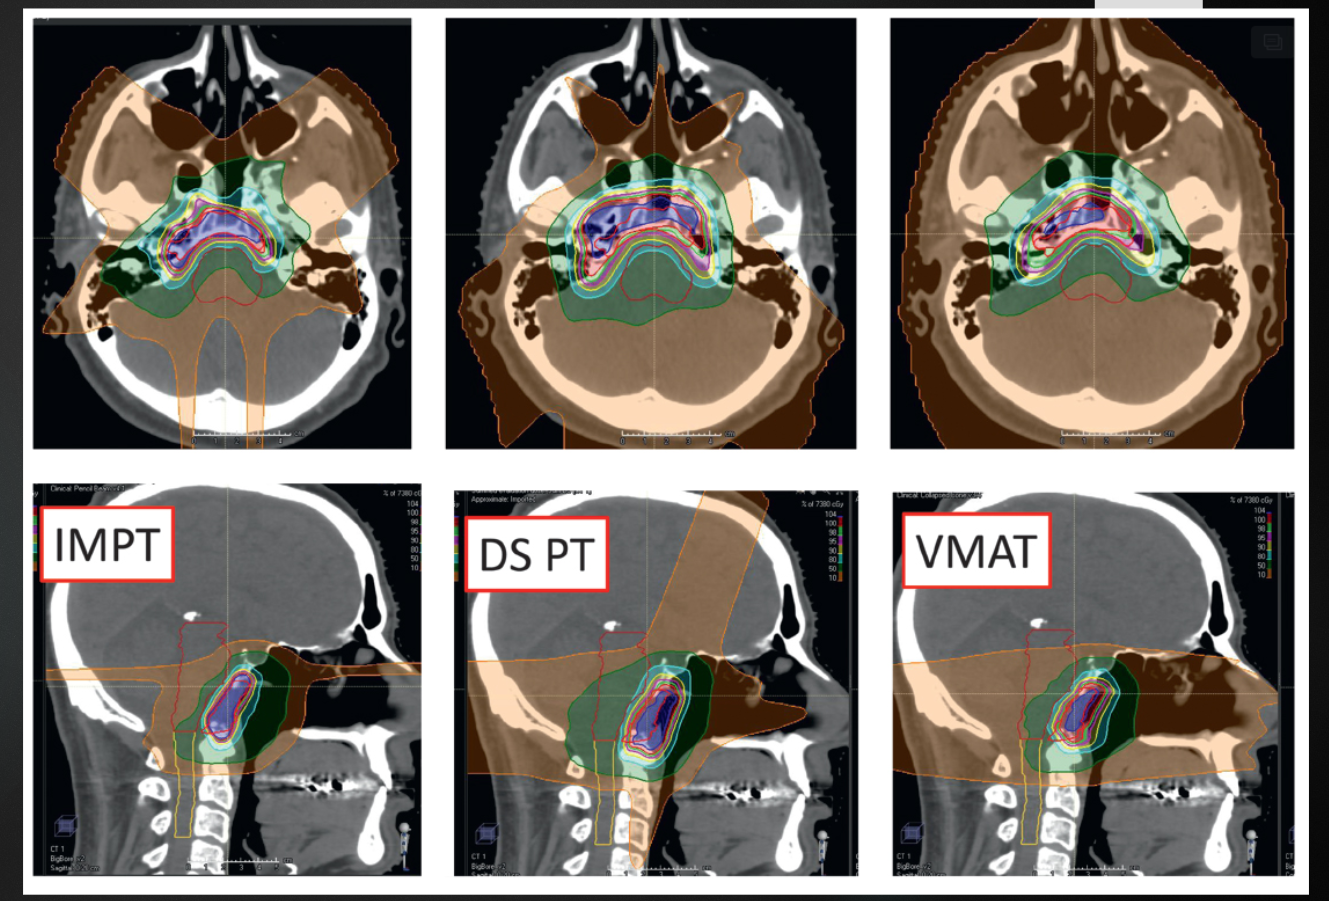

proton vs photon plans

A

How well did you know this?